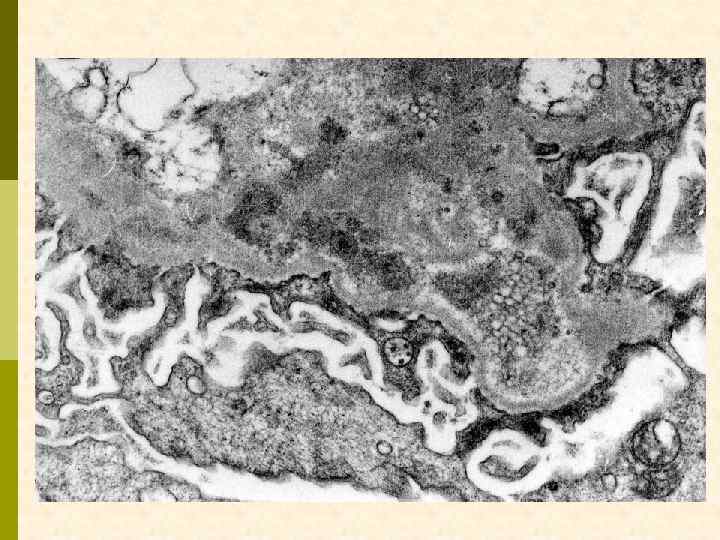

Характерные морфологические признаки ВИЧАН p почки больших размеров p тяжелое повреждение клубочков – коллаптоидный вариант ФСГС p расширение мезангия p гиперплазия и пролиферация подоцитов, аномалия висцерального и париетального эпителия клубочков – дедифференцирование ? ? ? p иммунные депозиты минимальны p атрофия канальцевого эпителия, кистозная дегенерация канальцев с заполнением их белковыми цилиндрами p нередкий тяжелый интерстициальный отек с моноцитарной (лимфоцитарной) инфильтрацией p нередко острый канальцевый некроз p ЭМ: тубуло-ретикулярные структуры в эндотелиоцитах клубочковых капилляров и других сосудов

ВИЧ-ассоциированная нефропатия. Тубулоретикулярные структуры в эндотелиоците.